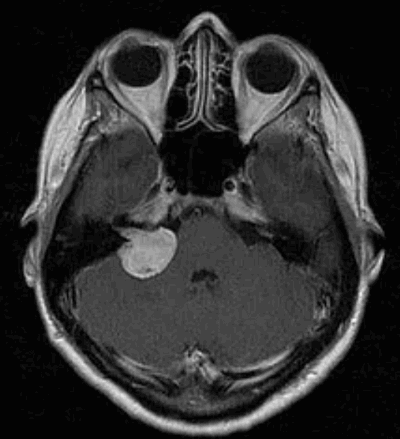

По данным МРТ головного мозга с усилением сигнала парамагнетиком выявлена опухоль парастволовой локализации справа, компримирующая продолговатый мозг и исходящая из расширенного канала подъязычного нерва. Меньший по размерам компонент опухоли располагался в полости канала и распространялся экстракраниально (рис. 1). Рис. 1. МРТ головного мозга пациентки В. до операции. При усилении сигнала выявляется опухоль справа, соответствующая невриноме, в форме «гантели», располагающаяся одной частью на уровне краниовертебрального перехода и вызывающая компрессию ствола мозга, а другой — частью в костных структурах.

Вестибулярная шваннома (невринома VIII нерва, акустическая невринома) представляет собой доброкачественное новообразование, возникающее из шванновских клеток вестибулярной порции VIII нерва.

Наиболее информативным методом выявления вестибулярных шванном является МРТ головного мозга с контрастным усилением в режиме Т1 и Т2. Это исследование позволяет определить размеры опухоли, наличие перитуморозного отека, наличие признаков окклюзионной гидроцефалии, которая может быть следствием сдавления опухолью IV желудочка. Кроме этого МРТ позволяет провести дифференциальную диагностику с другими опухолями схожей локализации (чаще с менингиомой задней грани пирамиды височной кости). Еще одним стандартом диагностики является КТ в костном режиме. Независимо от снижения слуха стандартом является проведение аппаратной аудиографии.